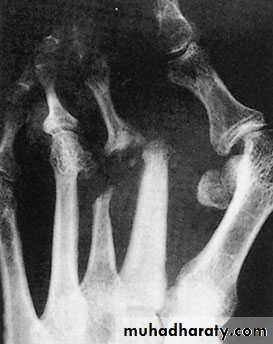

X-ray:

Taken with the patient standing to show the degree of metatarsal and hallux angulations.Also it shows the state of the joint being normal, arthritic or subluxated.